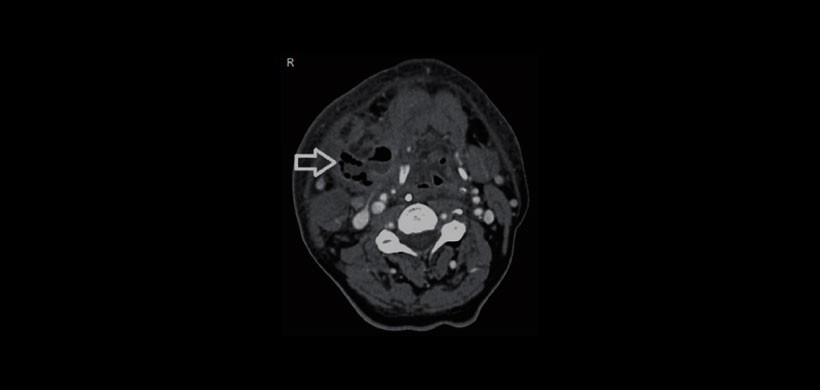

Paciente masculino de 66 años con quejas de fiebre, hinchazón en el cuello, enrojecimiento y falta de aliento. No se conoció diabetes o inmunodeficiencia en este caso. Al examen físico reveló una inflamación media que fue aproximadamente 10 cm de dimensión y era más grande de lado derecho del cuello. En el examen de laringoscopio las cuerdas vocales eran edematosas y tenían movimiento normal. La tomografía computarizada de cuello (CT) mostró sialoadenitis submandibular derecha y absceso inducida por un cálculo intraductal. (Figuras 1-3).

Como conclusión se llego al diagnóstico de Fascitis Necrotizante cervical, siendo la base del diagnóstico el estudio imagenológico que en esta ocasión se usó la Tomografía Computarizada.